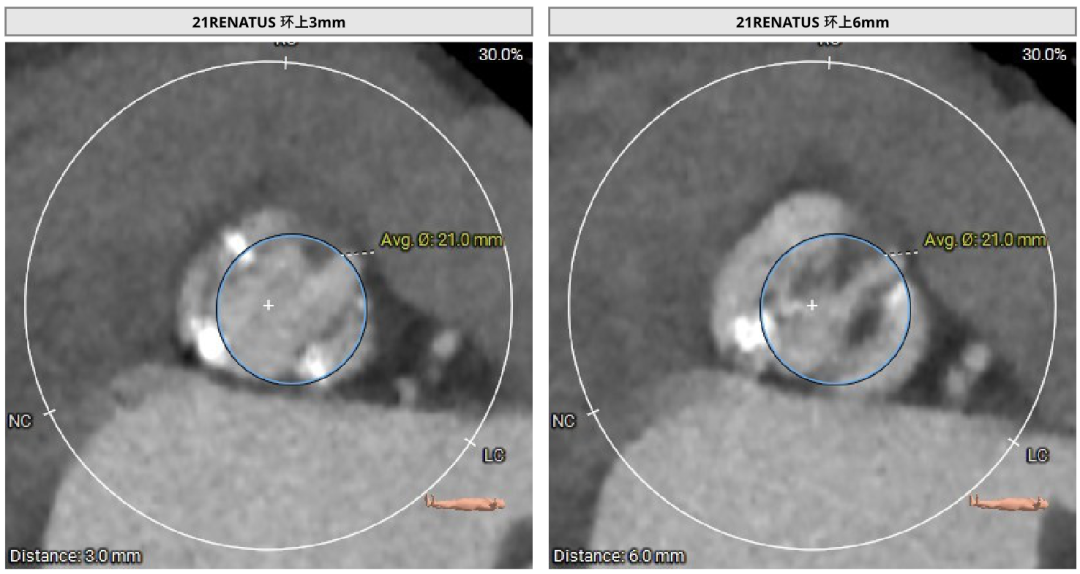

患者Type1 二叶瓣,右无融合,融合嵴钙化,钙化主要分布瓣叶缘和融合嵴处,无冠窦底钙化向下延伸至流出道4mm处。Annulus面积398mm²,LVOT面积400mm²,SOV 27.6-30.9mm,STJ高度21.3mm,内径29-32.7mm,瓣环角度62°,升主动脉扩张,左冠高度14.9mm,左冠瓣叶长度15.7mm,右冠高度15.8mm,右冠瓣叶长度9.2mm,模拟植入21#瓣膜VTC LCA 2.4mm,右侧髂内分叉处可见钙化,右侧髂外动脉最细为6.1mm,左侧髂外动脉最细为6.1mm,外周入路尚可。

左冠高度:High: 14.9mm

右冠高度:High: 15.8mm

左冠高度14.9mm,左冠瓣叶长度15.7mm,右冠高度15.8mm,右冠瓣叶长度9.2mm,模拟植入21#瓣膜VTC LCA 2.4mm